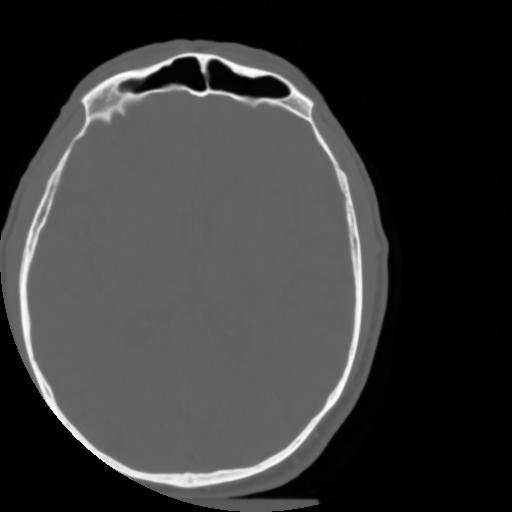

3 CEREBRO,,Axial,3.0,CEREBRO,,